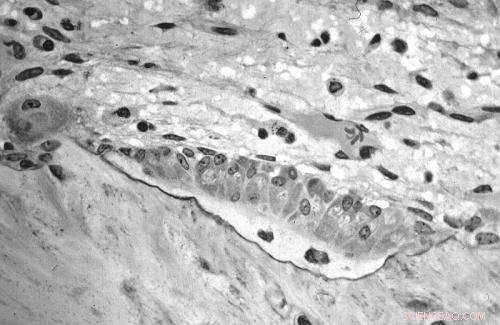

Osteoblasts actively synthesizing osteoid. Credit: Robert M. Hunt; Wikipedia.

A new study into the way bone cells organise during bone formation could open the door to a better understanding of diseases such as osteoporosis.

Dr Philip Kollmannsberger, who led the research, said: "Osteocytes and their cell processes 'live' in a large, interconnected network of voids permeating the mineralized bone matrix of most vertebrates. This osteocyte lacuno-canalicular network (OLCN) is believed to play important roles in sensing and maintaining the bone's constant internal environment, and for the mechanical properties of bone.